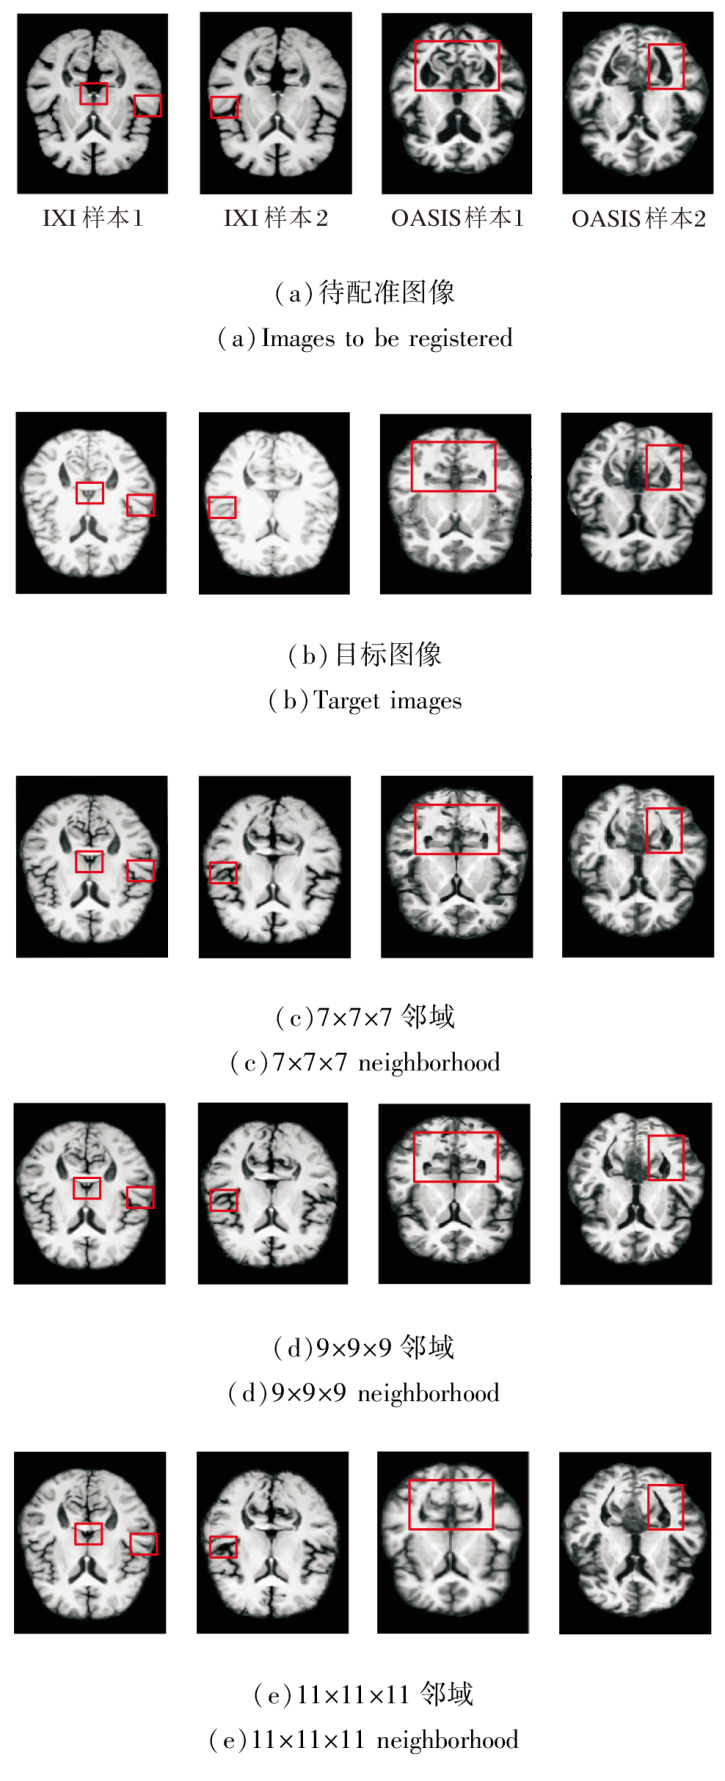

基于局部邻域内的像素强度统计相关性计算相似性损失函数, 邻域尺寸直接影响度量的鲁棒性.尺寸过小会导致局部采样不足, 难以捕捉完整的解剖强度分布, 降低对结构细节的敏感性; 尺寸过大容易引入无关区域的强度干扰, 模糊局部对应关系.为此, 本文设置7× 7× 7、9× 9× 9、11× 11× 11的邻域尺寸.

在IXI、OASIS数据集上各自选取2个样本, 邻域尺寸改变后图像配准结果如图19所示, 对PyraMLP-Net性能的影响如图20所示.

由图19和图20可见, 9× 9× 9邻域尺寸在DSC、HD95指标上均取得最优值.在IXI数据集上, 相比7× 7× 7邻域和11× 11× 11邻域, 9× 9× 9邻域的DSC值分别提高约0.6%和1.2%, HD95值分别降低约2.2%和8.3%.

在OASIS数据集上, 相比7× 7× 7邻域和11× 11× 11邻域, 9× 9× 9邻域的DSC值分别提高约0.7%和1.3%, HD95值分别下降约5.4%和9.5%.

性能差异源于不同邻域尺寸对图像噪声、解剖结构覆盖和相似性度量可靠性的影响.7× 7× 7邻域涵盖体素数量有限, 局部灰度均值容易受到图像噪声和伪影干扰, 降低相似性损失的稳定性, 从而影响配准精度.11× 11× 11邻域由于覆盖范围过大, 可能引入不相关解剖结构的干扰, 导致图像相似性度量无法准确反映目标解剖对应关系, 同样限制配准性能.相比之下, 9× 9× 9邻域在局部细节保留与噪声鲁棒性之间实现良好平衡, 既能抑制噪声敏感问题, 也能避免大邻域带来的结构混淆问题, 有效提高配准精度.